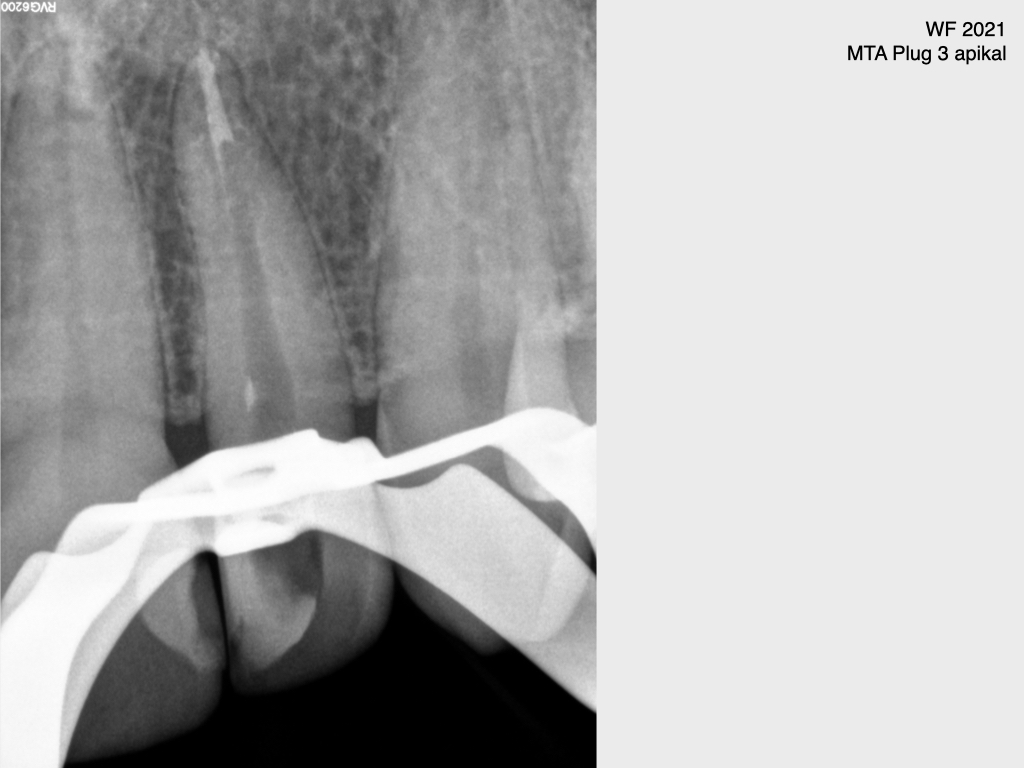

Frontzahn 22 (3)